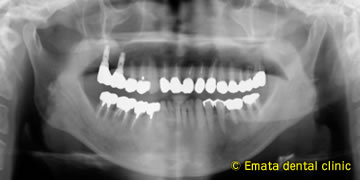

患者さんは、右上奥歯をインプラント治療を希望されて来院された62才の男性の方です。上顎洞底の位置が低く、CT撮影で外側の骨も喪失してることがわかりました。奥歯の上には上顎洞という空洞(黄色の矢印の線)がありこのままではインプラントが上顎洞内に突き抜けてしまうためインプラントの手術ができません。

インプラントが2本はいりました。上顎洞(黄色い線)があがったのがわかりますね。